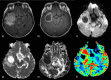

The role of conventional Magnetic Resonance Imaging (MRI) in the detection of cerebral tumors has been well established. However its excellent soft tissue visualization and variety of imaging sequences are in many cases non-specific for the assessment of brain tumor grading. Hence, advanced MRI techniques, like Diffusion-Weighted Imaging (DWI), Diffusion Tensor Imaging (DTI) and Dynamic-Susceptibility Contrast Imaging (DSCI), which are based on different contrast principles, have been used in the clinical routine to improve diagnostic accuracy. The variety of quantitative information derived from these techniques provides significant structural and functional information in a cellular level, highlighting aspects of the underlying brain pathophysiology. The present work, reviews physical principles and recent results obtained using DWI/DTI and DSCI, in tumor characterization and grading of the most common cerebral neoplasms, and discusses how the available MR quantitative data can be utilized through advanced methods of analysis, in order to optimize clinical decision making.